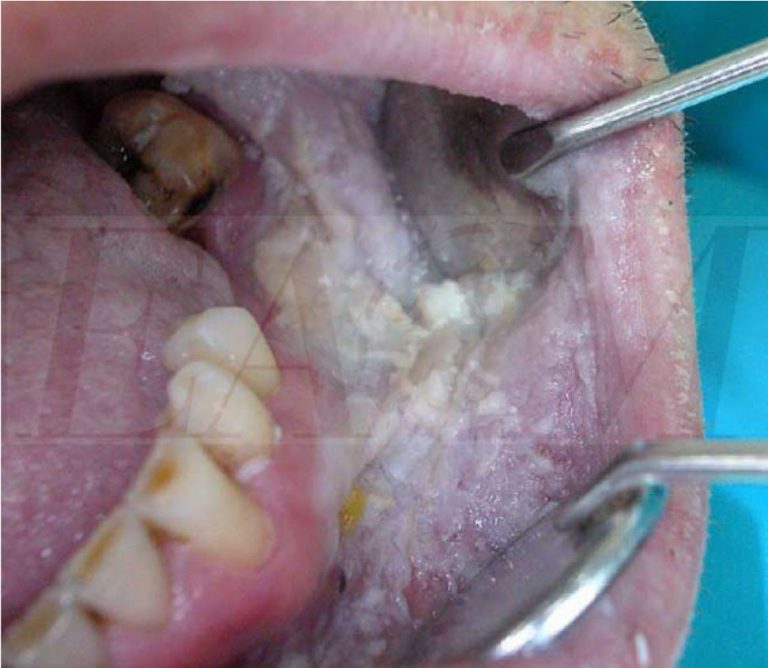

Oral White Sponge Nevus Histology . White sponge nevus (wsn) in the oral mucosa is a rare autosomal dominant genetic disease. The involved mucosa is white or greyish,. The involved mucosa is white or greyish,. The surface of the plaque is thick, folded and may. White sponge nevus (wsn) in the oral mucosa is a rare autosomal dominant genetic disease. White sponge nevus (wsn) is an uncommon, hereditary benign keratinization defect that primarily affects the oral mucosa and occasionally, though rarely, the skin or other mucosal sites, such as the nose, esophagus and White sponge nevus is an autosomal dominant skin disorder characterized by white, irregular, diffuse plaques mainly affecting the oral. Benign keratinization defect leading to white plaques on mucosa. White sponge nevus (wsn) is a rare, autosomal dominant hereditary disorder with a high degree of penetrance and variable expression. Leukoedema and white spongy nevus are two conditions with a similar histologic feature showing hyperparakeratosis, acanthosis, and.

White sponge naevus an oral white lesion BMJ Case Reports Oral White Sponge Nevus Histology White sponge nevus is an autosomal dominant skin disorder characterized by white, irregular, diffuse plaques mainly affecting the oral. White sponge nevus (wsn) is a rare, autosomal dominant hereditary disorder with a high degree of penetrance and variable expression. The surface of the plaque is thick, folded and may. White sponge nevus (wsn) is an uncommon, hereditary benign keratinization defect. Oral White Sponge Nevus Histology.